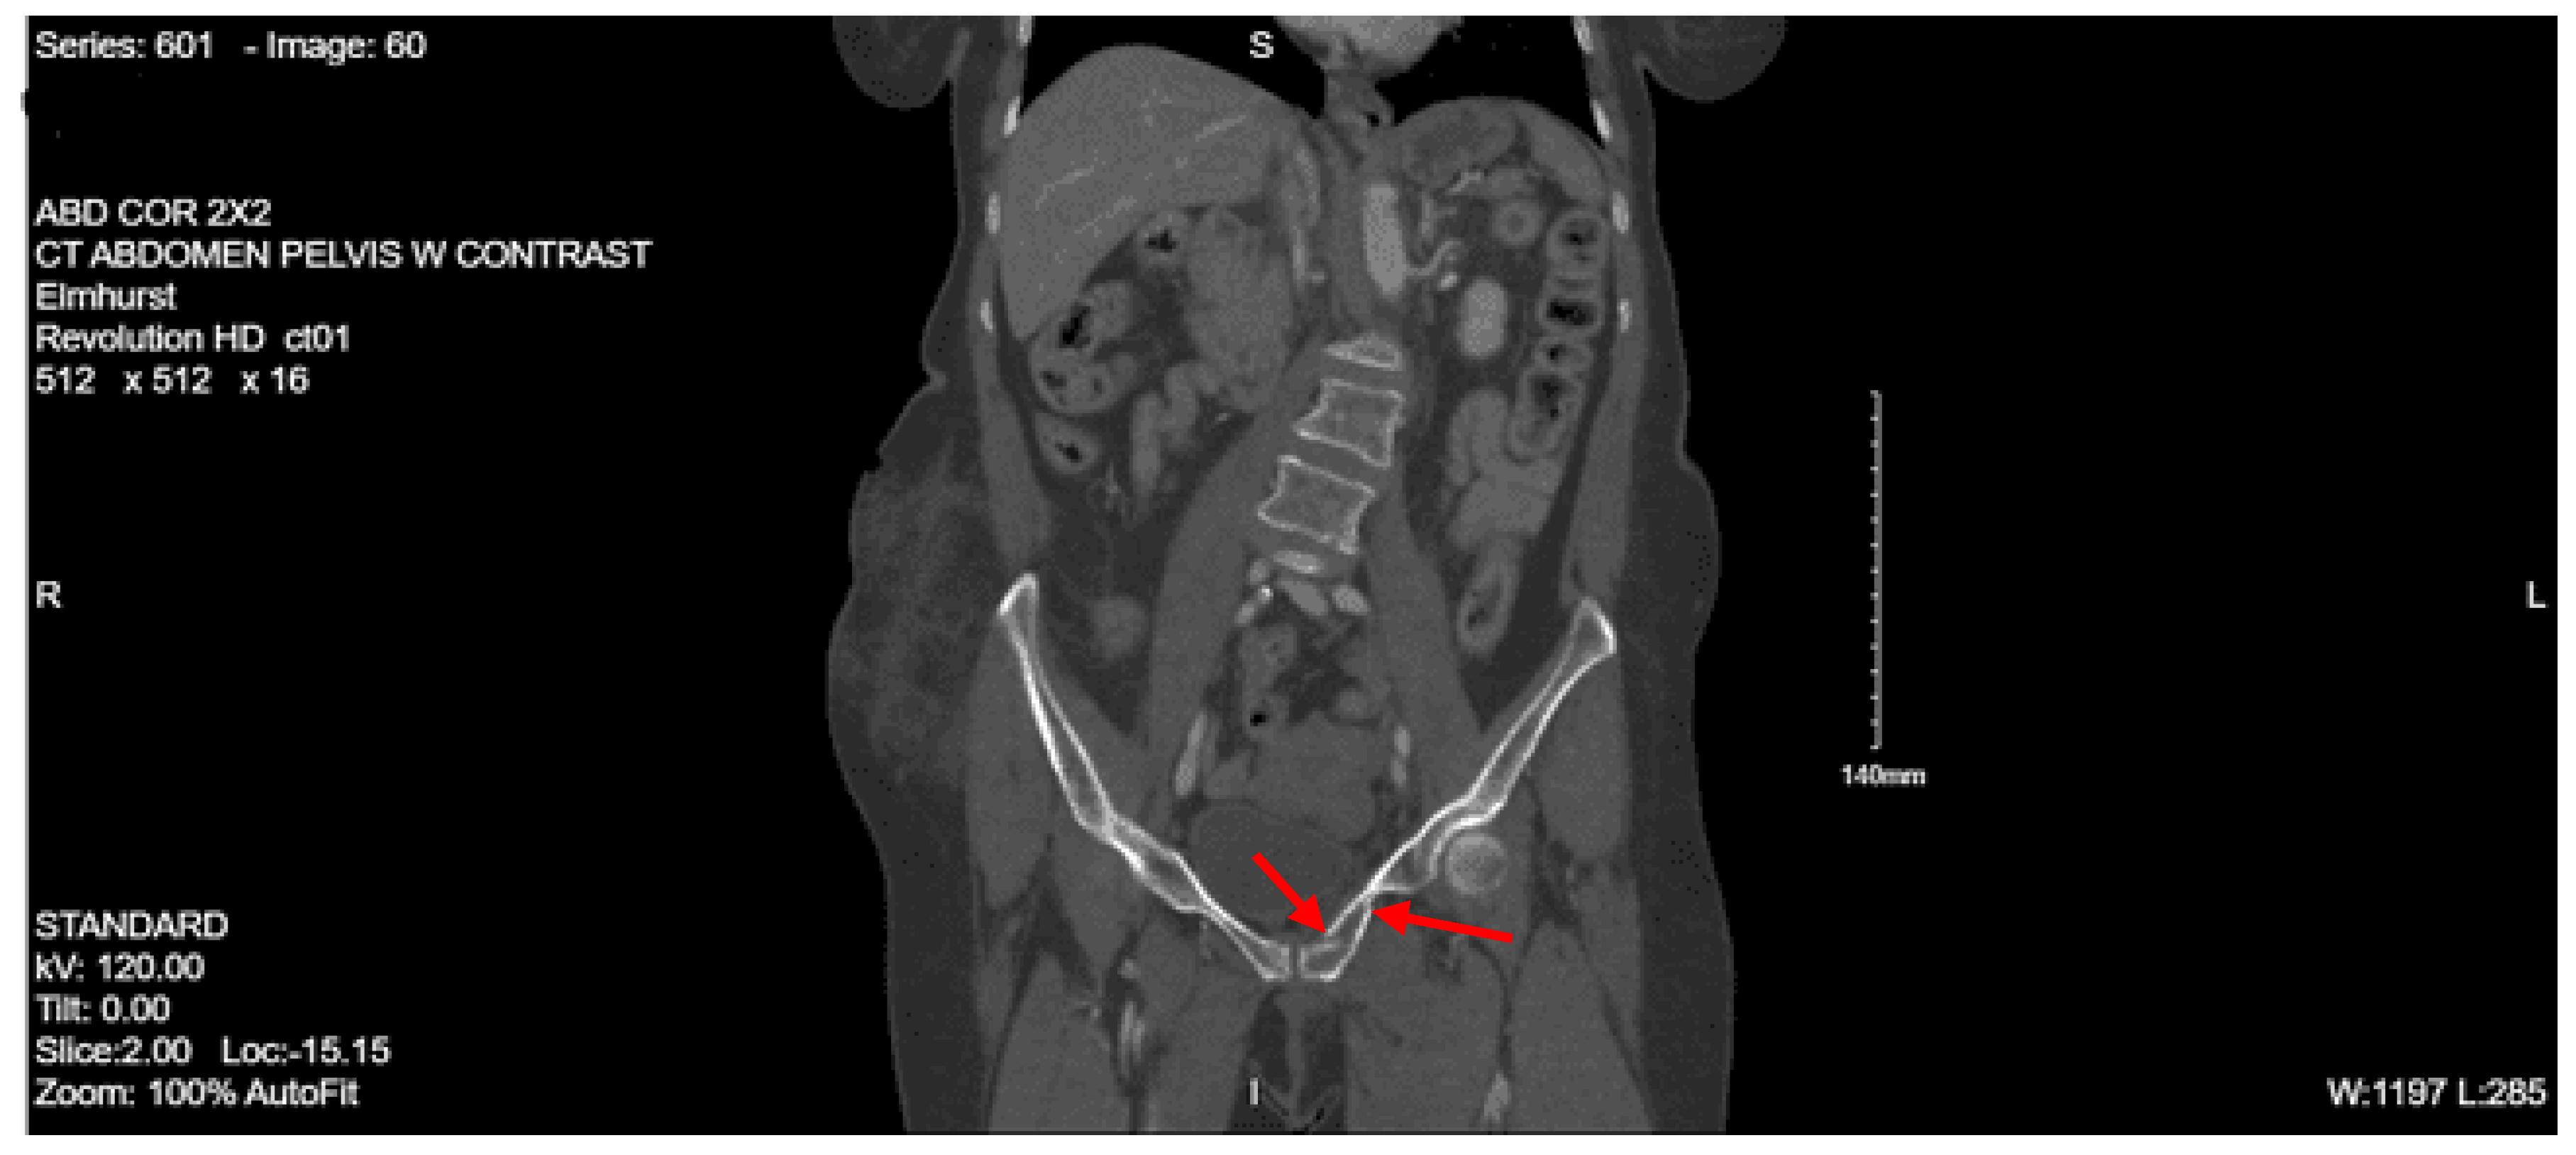

Imaging as shown in Figure 4, Figure 5 and Figure 6:

Portable pelvis x-ray: Acute impacted fracture involving the left superior pubic ramus in its medial aspect. Possible fracture, which is nondisplaced, involving the left inferior pubic ramus. The right superior and inferior pubic rami are intact. Femoral acetabular joints were unremarkable.

CT abdomen and pelvis with contrast: No acute visceral traumatic abnormality. There is evidence of an acute impacted fracture involving the left superior and inferior pubic rami. The right superior and inferior pubic rami are intact. The sacrum and coccyx appear unremarkable.

During her hospital course, the patient was also found to have a right lateral tibial plateau fracture and bilateral sacral ala fractures; orthopedic surgery recommended non-weight bearing for the RLE, and neurosurgery recommended bed rest. She required multiple blood transfusions due to repeated drops in hemoglobin/hematocrit but remained hemodynamically stable. Given her continued intubation status, tracheostomy was performed on hospital day 8. Continued monitoring via CT head with and without contrast continued to show evolving strokes and persistent severe vasospasm. On hospital day 13, the patient was seen by physical medicine and rehabilitation, who recommended physical and occupational therapy and TBI unit vs sub-acute rehab for discharge when the patient was medically stable. The patient’s mental status gradually started to improve, and she was transferred to the surgical stepdown unit on hospital day 15. On hospital day 19, PEG was placed by interventional radiology. The patient continued to slowly improve, and tracheostomy decannulation was performed on hospital day 36; then she was discharged to TBI rehab 3 days later.